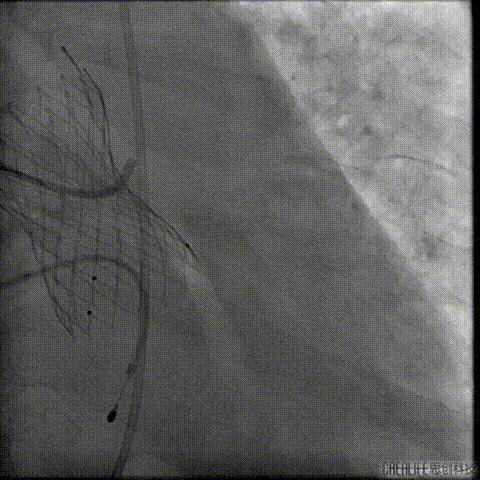

经瓣架网眼挂上指引管

反复确认指引管经瓣架网眼

指引管经瓣架网眼

经网眼置入导丝

置入4.0mm*23mm微创冠脉支架

定位并释放支架

退出球囊扩张突入瓣架部位

复查冠脉造影

多体位复查冠脉造影